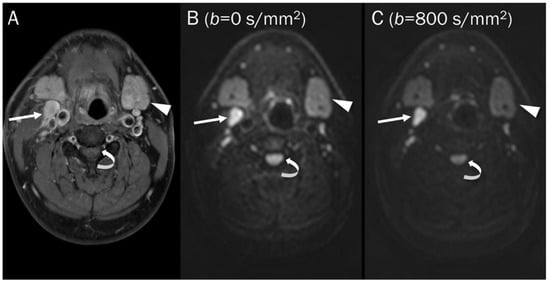

7.1. Cyst

5.1. T2 Shine-through Effect

5.2. T2 Black-out Effect